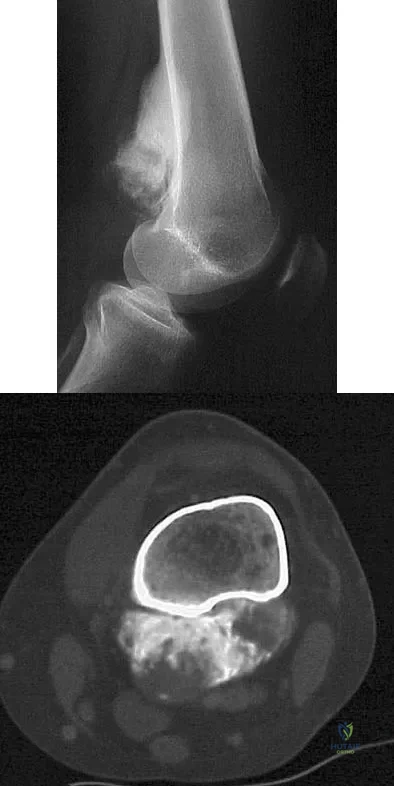

A 13-year-old patient has foot drop and lateral knee pain. AP and lateral radiographs and an MRI scan are shown in Figures 49a through 49c. A biopsy specimen is shown in Figure 49d. What is the preferred method of treatment?

Explanation

A 15-year-old girl has left knee pain and an enlarging mass in the distal thigh. AP and lateral radiographs are shown in Figures 52a and 52b, and a biopsy specimen is shown in Figure 52c. What is the most likely diagnosis?

Explanation